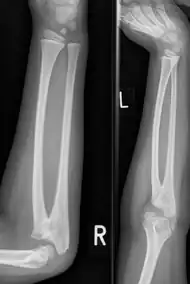

Plain radiograph showing fusion of the radius and ulna

Congenital radioulnar synostosis in a 7 year old boy

Radioulnar synostosis is a rare condition where there is an abnormal connection between the radius and ulna bones of the forearm.[1] This can be present at birth (congenital), when it is a result of a failure of the bones to form separately, or following an injury (post-traumatic).[2]